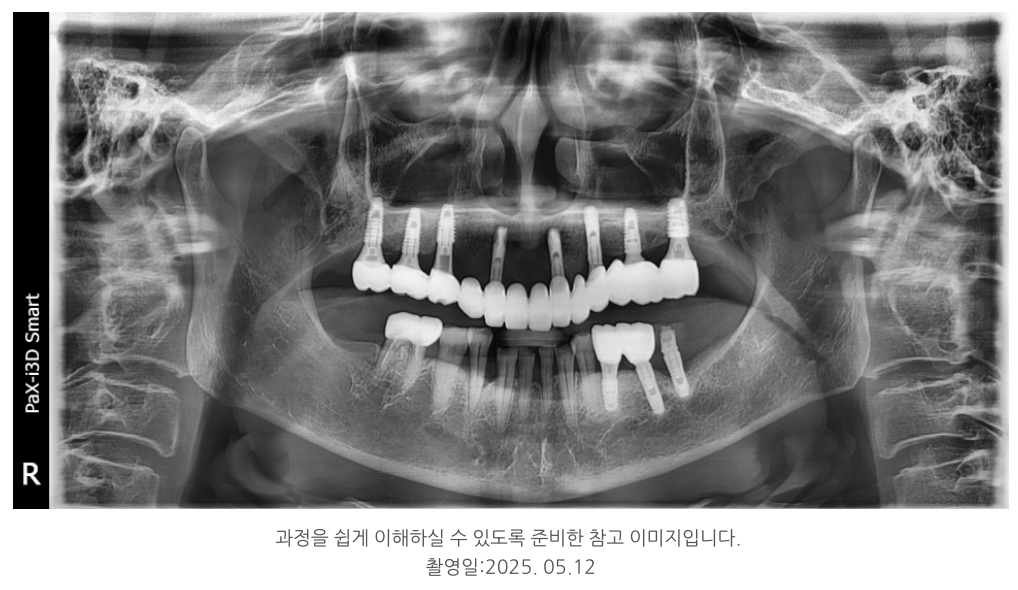

기존 임플란트 중 상태가 양호한 2개는 보존하고,

부족한 부위에는 새로 6개를 심어 총 8개로 구성했습니다.

이로써 힘이 고르게 분산되도록 설계했고,

부족한 뼈에는 뼈이식을 병행해 안정성을 높였습니다.